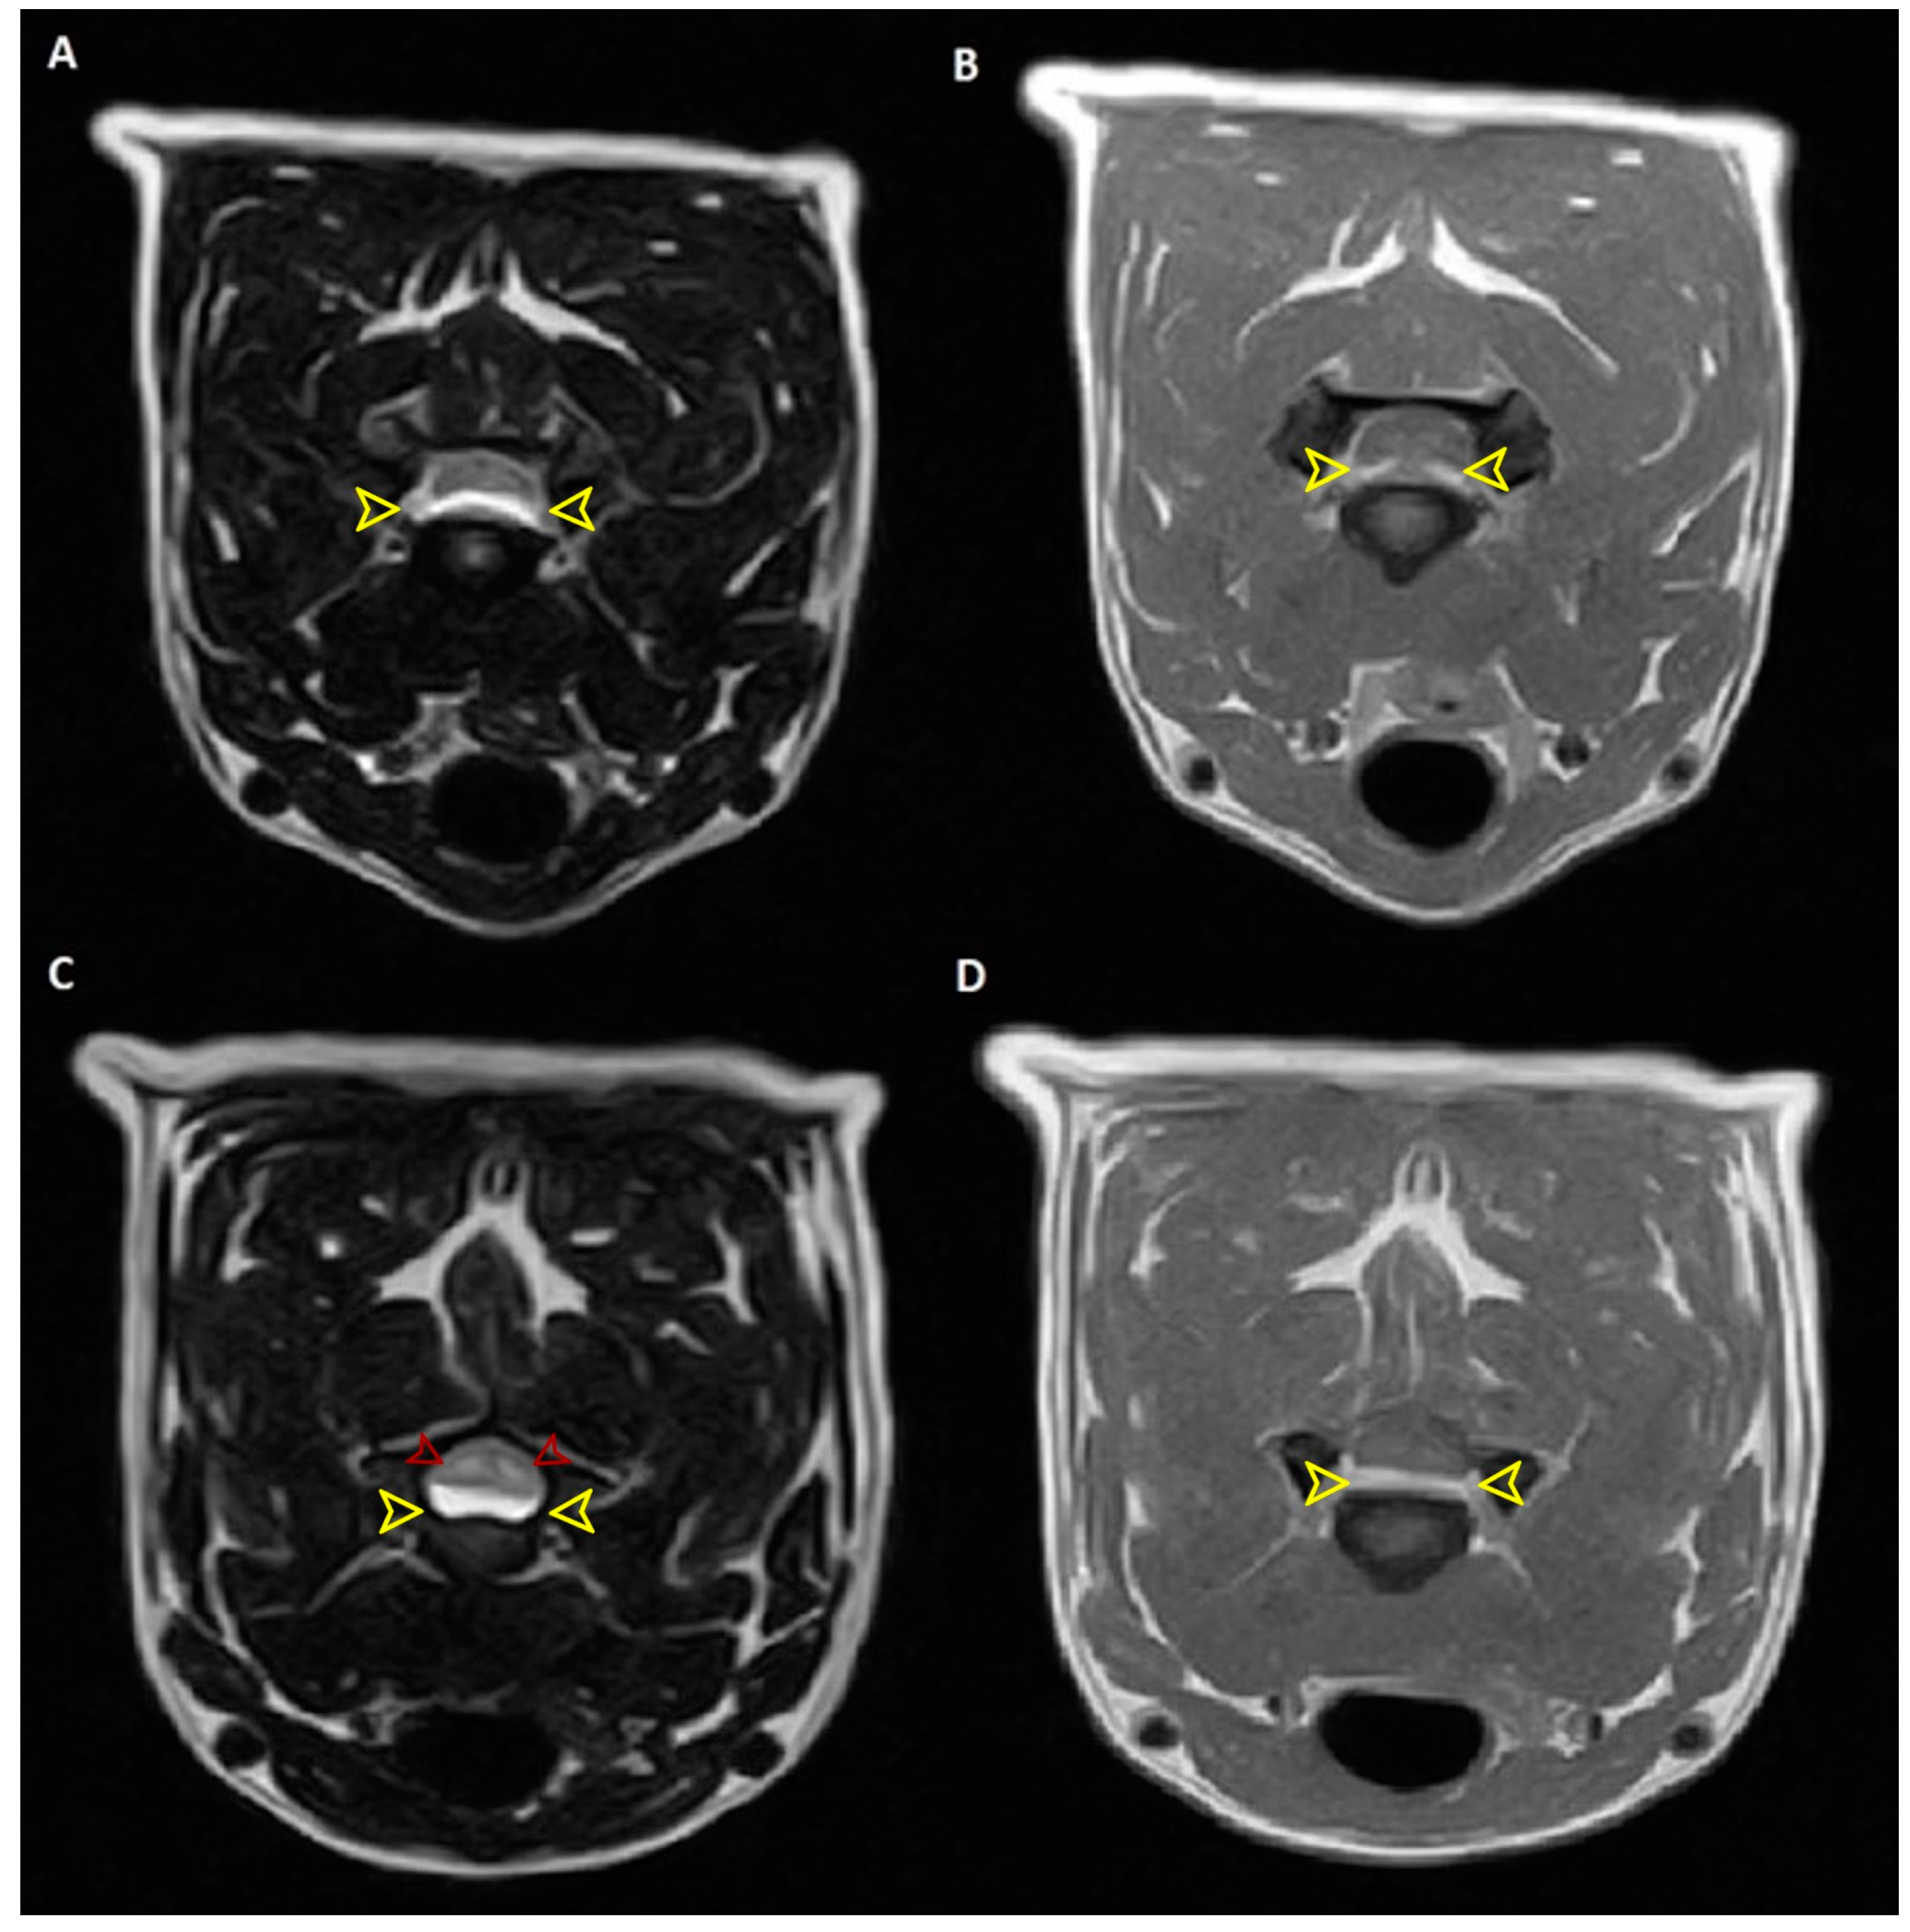

2. Case Description